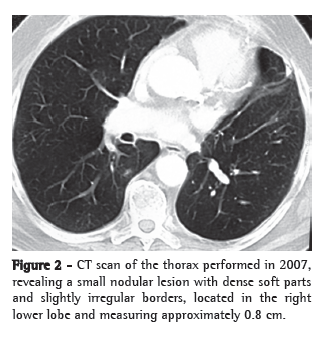

We present the case of a 71-year-old male patient submitted to left upper lobe lobectomy with pericardial resection due to localized invasion and mediastinal lymphadenectomy five years ago (Figure 1). The pathological stage was IIB (T3N0M0). A contralateral pulmonary lesion (0.8 cm) was found in the upper segment of the right lower lobe during a follow-up imaging study (Figure 2). This lesion had not been seen in previous imaging studies. The patient was asymptomatic, had no comorbidities and presented no history of liver disease. He was a former smoker (30